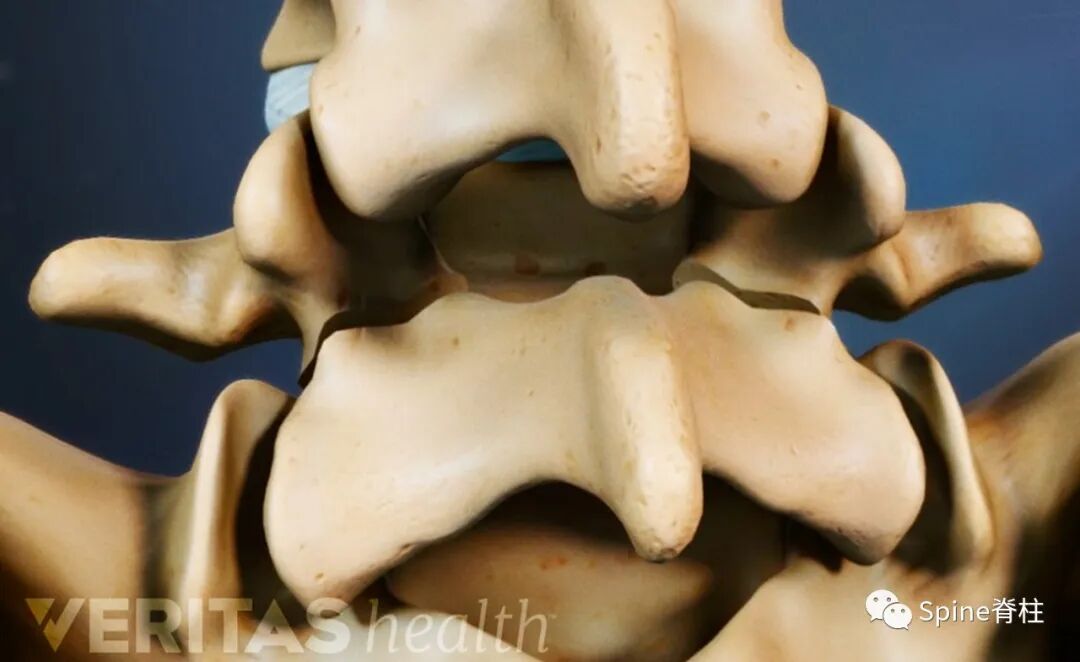

峡部 (pars interarticularis)是指上、下关节突之间椎弓的狭窄部分,又称为关节突间部(人卫版八年制外科学)。因腰椎峡部裂相对比较常见,‍学者们的峡部研究常关注于腰椎。其实,从C2-L5各节段脊柱都是存在峡部。

峡部是在相邻节段平移运动中承受应力最大的部位,C2和L5的峡部最易发生创伤性或应力性骨折 (如C2的hangman骨折和L5峡部裂)。峡部构成椎管侧隐窝的后部,并参与构成神经根管的后壁。

L5脊椎骨背面斜位示意图。显示椎弓的各部分:阴影区1=峡部,2=椎板,3=椎弓根。虚线处为峡部裂的常见部位。